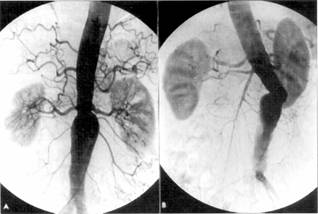

Aortografia consta in vizualizarea aortei si a ramurilor sale prin injectarea unei substante de contrast. Tehnica aortografiei difera cu portiunea pe care dorim sa o exploram. Astfel, distingem: aortografia toracica si aortografia abdominala.

Aortografia abdominala

Abordarea aortei abdominale se realizeaza prin punctie translombara (metoda directa) sau pe cale femurala prin cateterism retrograd dupa metoda Seldinger sau Hettler (mai sus descrisa).

Aortografia translombara: bolnavul asezat in procubit este punctionat cu ajutorul unui ac lung, cu bizou scurt, la 8-10 cm in afara liniei mediane, sub marginea inferioara a coastei a 12-a din stanga. Directia acului este oblica in sus si spre linia mediana catre vertebra a 12-a toracala. Momentul punctionarii vasului este marcat de senzatia patrunderii in gol si de evidentierea unui jet sanguin rosu-deschis abundent si pulsatil. Prin intermediul unui tub intermediar de polyetilen se adapteaza la ac seringa cu substanta de contrast nonionica 40-60 ml (incalzita la temperatura corpului) si se injecteaza manual cu maxim de forta, efectuandu-se radiografii innainte de ultimii 3-4 ml de substanta de contrast.

Aortografia femurala: bolnavul asezat in decubit dorsal este punctionat la nivelul arterei femurale in triunghiul lui Scarpa cu acul Seldinger in sens retrograd curentului sanguin. Dupa reusita punctiei se introduce mandrenul ghid si se scoate acul din artera. Pe mandren, prin miscari de rasucire, se introduce in lumenul arterial cateterul, care este condus pana la nivelul lui T12-L1. Se scoate mandrenul si se adapteaza cateterul la seringa de injectare sub presiune. Cu ajutorul seriografului se efectueaza radiografii, permitandu-se in felul acesta vizualizarea nu numai a aortei ci si a femuralelor, arterelor gambei, pana la arterele digitale. Prin folosirea cateterului cu varful curbat se pot vizualiza ramurile viscerale ale aortei abdominale, constituind arteriografia selectiva.